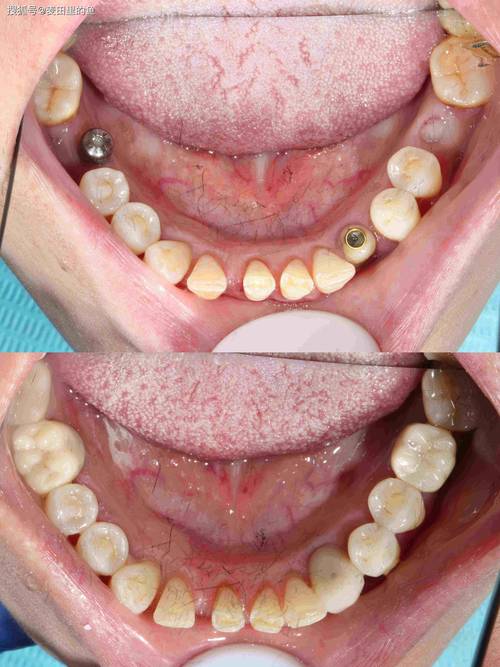

骨结合完成后,进入修复阶段,主要包括取模、制作牙冠及戴牙。

- 二期手术(若为埋植式种植体):对于埋植式种植体(种植体顶部完全埋入牙龈下),需行二期手术切开牙龈,暴露种植体基台连接部位,安装愈合基台,让牙龈形成袖口,2-4周后取模。

- 取模:采用数字化印模(口内扫描仪)或传统印模(用聚醚硅橡胶或聚加硅橡胶取模),获取精确的种植体及周围牙龈形态,送技工室制作牙冠。

- 牙冠制作与戴牙:磨牙区牙冠需承受较大咬合力,材料通常选择全瓷冠(如氧化锆全瓷冠)或金属烤瓷冠,强度高、耐磨性好,技工室制作完成后,医生试戴牙冠,检查边缘密合度、颜色、形态及咬合关系(调整咬合避免早接触、创伤颌),确认无误后用粘接剂固定(种植体基台通常采用粘接固位或螺丝固位)。